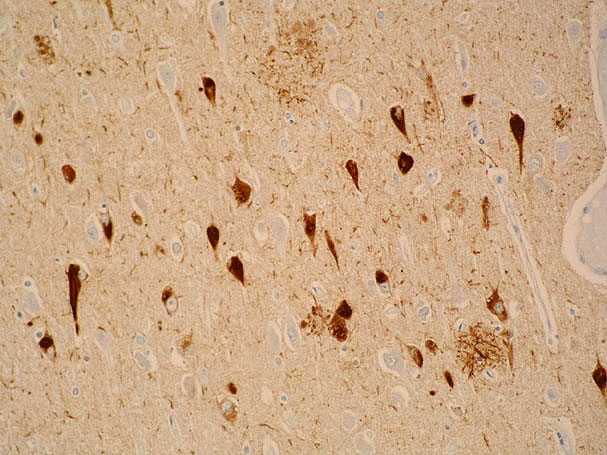

Alfa-sinucleína